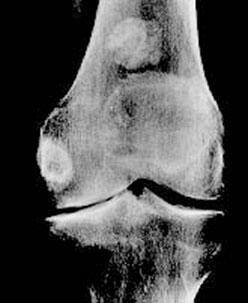

![]() |

Une étude a enrôlé 85 personnes avec une arthrose du genou et les a suivis pendant six mois. Les participants ont reçu 400 mg de sulfate de chondroïtine deux fois par jour ou un placebo. À la fin de l'essai, les médecins ont évalué les améliorations comme bonnes ou très bonnes chez 69 % des personnes prenant du sulfate de chondroïtine et chez seulement 32 % des sujets sous placebo. Une autre façon de comparer les résultats est de regarder la vitesse maximum de marche des participants. |

Alors que les sujets du groupe prenant de la chondroïtine ont été capables d'améliorer graduellement leur vitesse de marche au cours de l'étude, cela n'a pas été le cas dans le groupe sous placebo. D'autres améliorations ont également été constatées dans les mesures de l'arthrose comme le niveau de douleur avec des bénéfices dès le premier mois de traitement. Ces résultats suggèrent que le sulfate de chondroïtine peut empêcher l'arthrose de s'aggraver progressivement (Bucsi L. et al., 1998). |